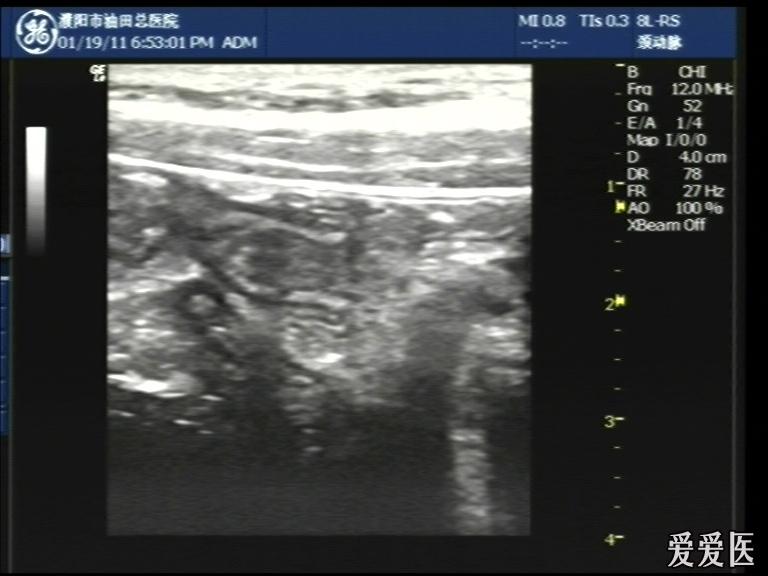

超声检查:于下腹部可见“双环征象”,双环重叠长约6mm,检查期间观察可见肠蠕动;CDFI:未见明显异常血流信号。

超声提示:下腹部双环征,考虑肠套叠可能,请结合临床

“套筒征”、“同心圆征”,很清晰,很经典!

好图,同心圆征。清晰